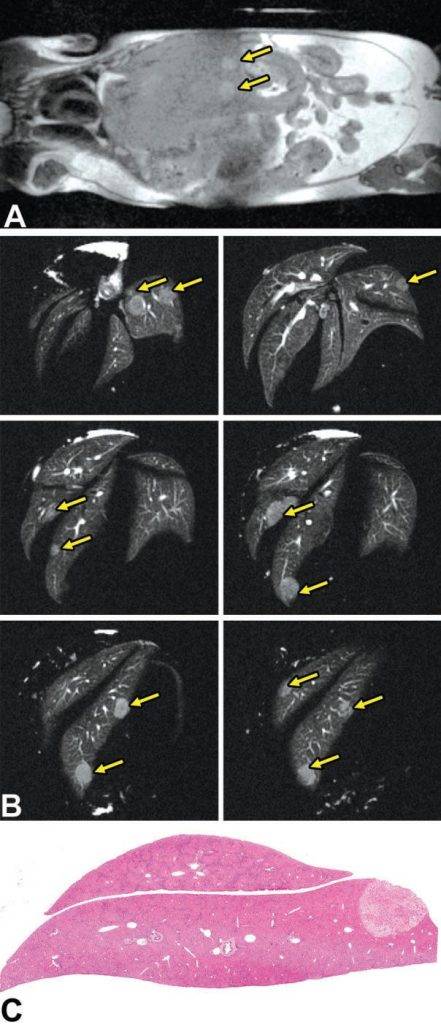

In vivo MRI detected focal liver injury in a mouse model (Fig. A). High-resolution ex vivo MRH identified several distinct focal fatty lesions in the liver (Fig. B and C). Routine histopathology confirmed these lesions as focal fatty changes (Fig. C).